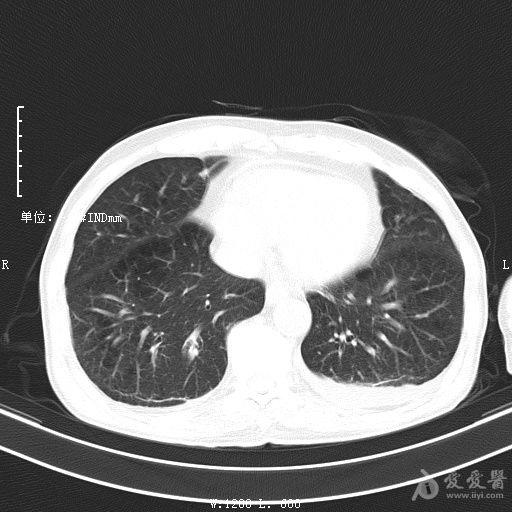

最新的肺炎疫情形勢嚴峻,病毒變異使得防控工作更加復雜,許多地方出現了新的病例,甚至有些地區的疫情出現了反彈,這不僅是對醫療系統的考驗,更是對每一個(gè)生命的考驗,我們需要密切關(guān)注疫情動(dòng)態(tài),共同應對這場(chǎng)挑戰。??